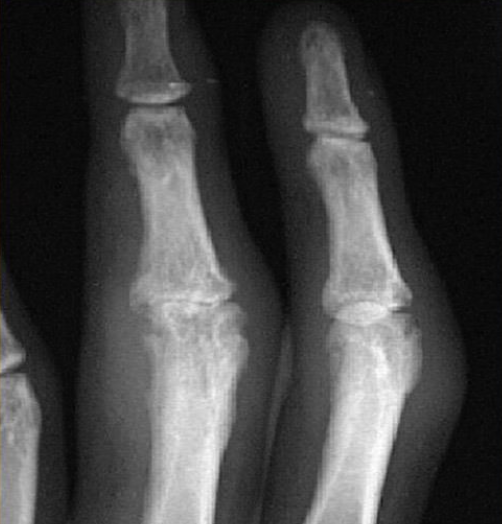

Name 2 radiological abnormalities?

a. Erosion of proximal interpharyngeal joint

b. Swelling of the in the middle finger

c. sublaxation of the joints -

What is likely etiology of arthritis

a. rheumatoid arthritis -

Which blood test will you do for diagnosis?

ACPA , RF